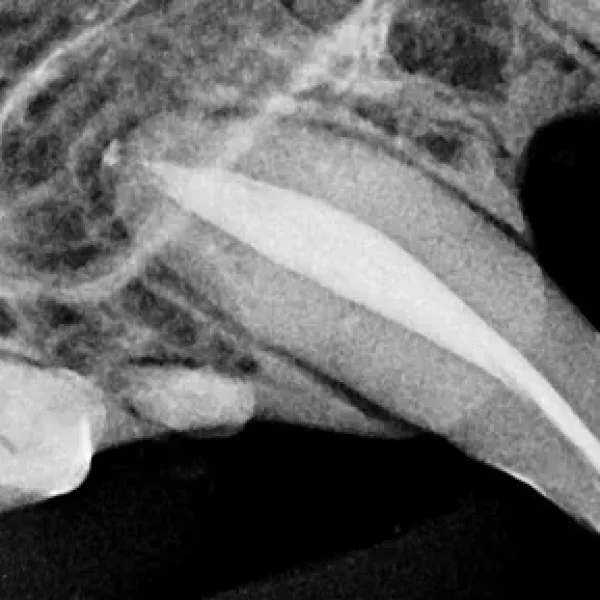

Fractured Teeth in Cats

Fractured teeth in cats can result from fights, car accidents, and chewing on hard objects. There are five classifications of tooth fractures and each needs treatment to avoid tooth sensitivity and pain. Because cats have thin enamel, even a small chip fracture can cause pain and needs veterinary care. Clinical signs include chewing on one side of the mouth, excessive drooling, pawing at the mouth, and facial swelling.